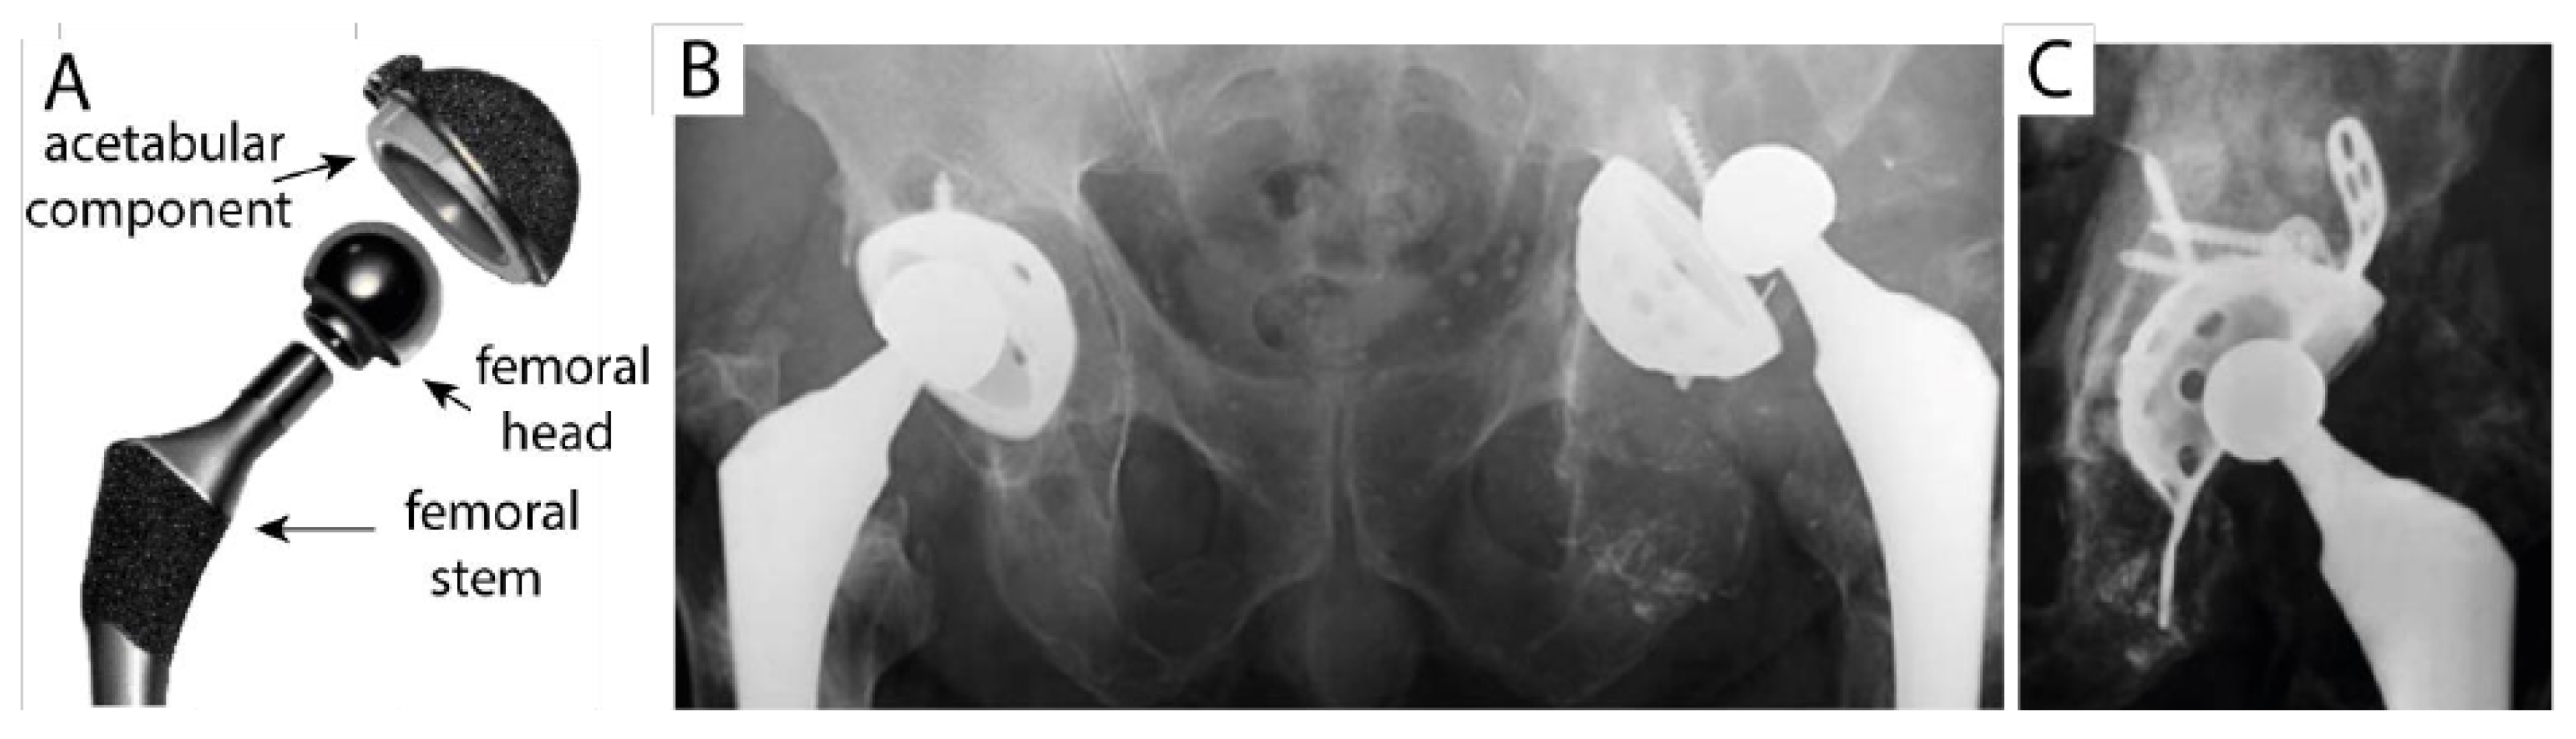

The main components of a hip implant are the femur head and the acetabular cup (Figure 2A), which typically consists of either a ceramic or a polymeric liner housed in the so-called “metal back”, which is fixed to the patient’s pelvic bone [20,21]. While a “sandwich” design with a polymer layer between ceramic liner and acetabular cup has been tried, research on it has been discouraged by lower than average survival rates [22]. An all-ceramic acetabular cup, on the other hand, allows for a simpler monoblock design [23]. The prosthetic femur head is inserted into the femur bone after removal of the surgically resected original head: the femur stem holds a ball on top of it which is part of the ball and socket coupling that constitutes the prosthetic hip joint. The acetabular cup is the socket, and it is inserted in the pelvic bone. Joining the cup to the bone can be accomplished in many ways: however, the modern design of hip prostheses favours cementless acetabular cups, with a porous outer surface optimized for osseointegration [23]. The main issues are bone resorption, especially near the acetabular cup (Figure 2B,C), and loosening of the mechanical joint. High biocompatibility and cytocompatibility are needed to avoid bone resorption: this is regulated by wear particle release and the nature of debris, as well as the chemistry of materials and the stability and surface morphology of the implant. On the other hand, certain mechanical properties are also needed in order to obtain the longest possible lifespan and minimum particle release. In this regard, high wear resistance is very important, as is hardness, a low wear rate, good flexural strength and high fracture toughness. These properties are all exhibited by ceramic materials that are also very stable from a chemical viewpoint. However, not all ceramics exhibit the same performance. For example, instability in the structure of zirconia under high stress and high humidity (tetragonal to monoclinic phase transformation) makes its fate unpredictable for long-term applications [24]. This is the reason why pure zirconia implants were withdrawn from the market and replaced by stabilized zirconia or alumina/zirconia composites (tradenamed as “Biolox delta”) [25]. Alumina is still commercially available (tradenamed as “Biolox forte”), but its fracture toughness has proven insufficient under certain circumstances with the remote possibility of catastrophic failure, thus discouraging doctors from more widespread adoption and favouring “Biolox delta” instead. A recent study also highlighted that fracture in modern ceramic liners (“Biolox forte” and “Biolox delta”) is mainly due to surgical errors/malpositioning rather than to inherent defects of the materials, which should virtually be nonexistent in certified commercial products [26].